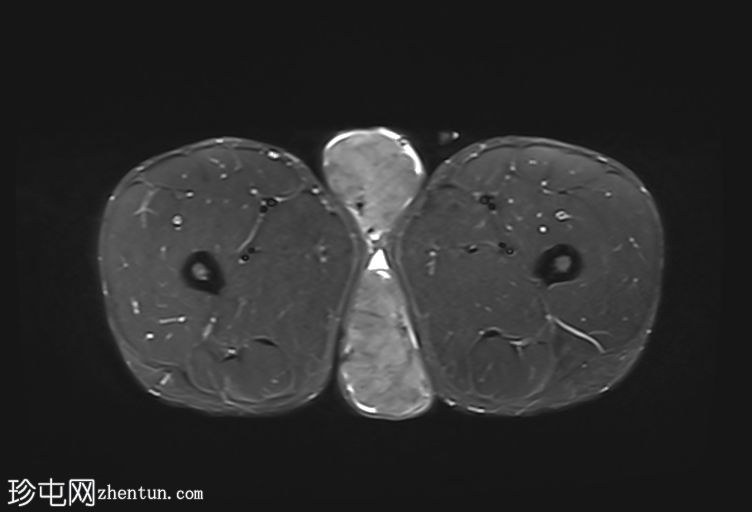

轴位

T2加权像

阴囊内睾丸增大,T1加权像上可见分叶状软组织病变,呈中高信号,T2加权像上呈低信号。

轻度双侧鞘膜积液。

本病例表现为双侧睾丸肿胀,影像学特征符合睾丸肾上腺残余肿瘤的典型表现,即T1加权像上呈双侧中高信号,T2加权像上呈低信号。